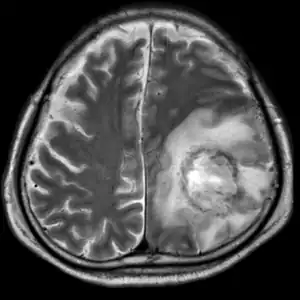

| T2-weighted MRI showing liquefied, necrotic brain tissue as a result of GAE caused by an infection of Acanthamoeba, genotype T18 | |

.png.webp)

B: T1-weighted MRI showing expansion and addition of necrotic areas 4 days later